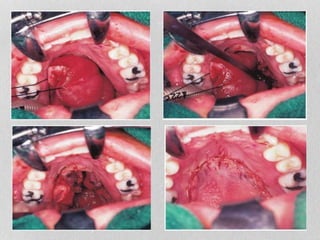

•Intraoral transpalatal approach: (Wilson’s)

 Allows for access to NP (for small lesions)

•Intraoral transpalatal approach:(Wilson’s)  Allows for access to NP (for small lesions)

• 47.